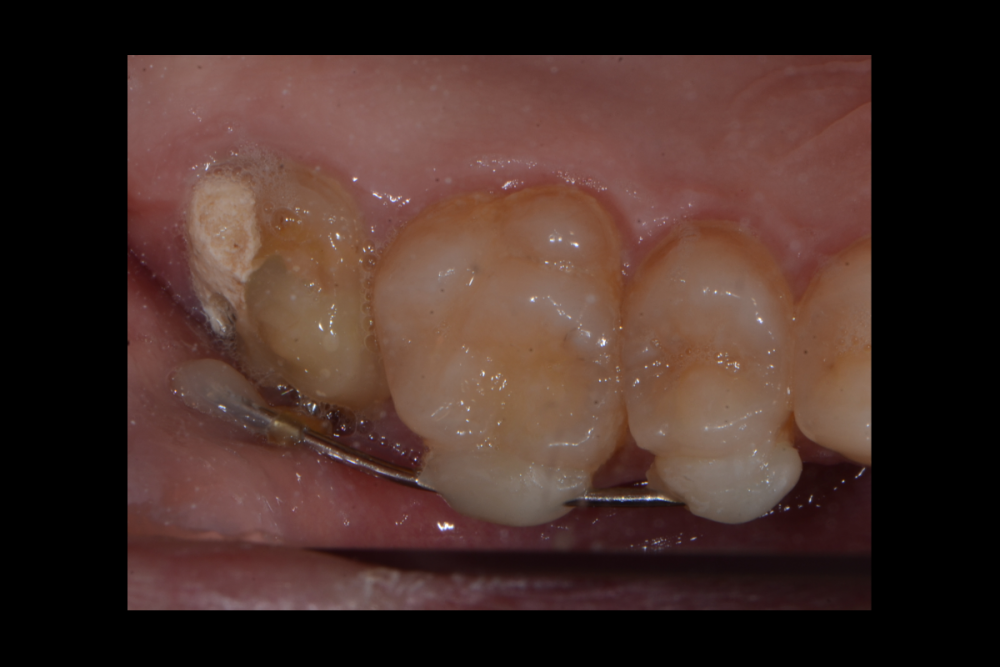

Карен Аванесов Опубликовано 20 сентября, 2021 Поделиться Опубликовано 20 сентября, 2021 (изменено) одномоментной установки имплантата, без вторжения в верхнечелюстной синус, регионарная мягкотканная пластика, выгодная ортопедическая ангуляция, не выгодной небной лунки. Пустоты заполнены губкой дигестол, дополнительная герметизация ликвидам. Мой только хирургический протокол, пациент реферативный. Время работы от удаления до имплантации 40 минут, ожидание до протезирования 3 месяца. Кейс посвящаю одноглазому и зеленому хулигану, любителю пива и девок, не знаю куда он делся, но пусть не грустит, все будет хорошо! Изменено 20 сентября, 2021 пользователем Карен Аванесов 10 1 1 Ссылка на комментарий

Карен Аванесов Опубликовано 22 сентября, 2021 Автор Поделиться Опубликовано 22 сентября, 2021 10 минут назад, сирена сказал: Красота. А рентгена нет? Мерси) есть, но тогда, красоту испорчу) Этой работе 4 года, пациент все никак на контроль, перед ковидом собирался и локдаун... как придет покажу. Ссылка на комментарий